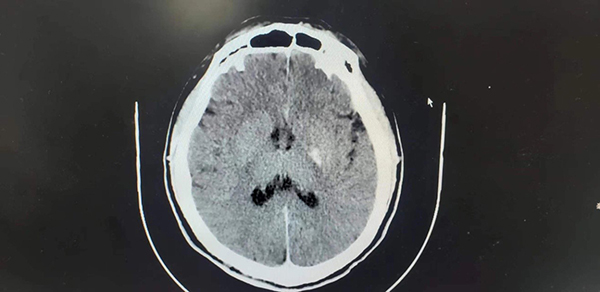

術(shù)后復(fù)查CT,組織窗效果滿(mǎn)意,提示預(yù)后良好